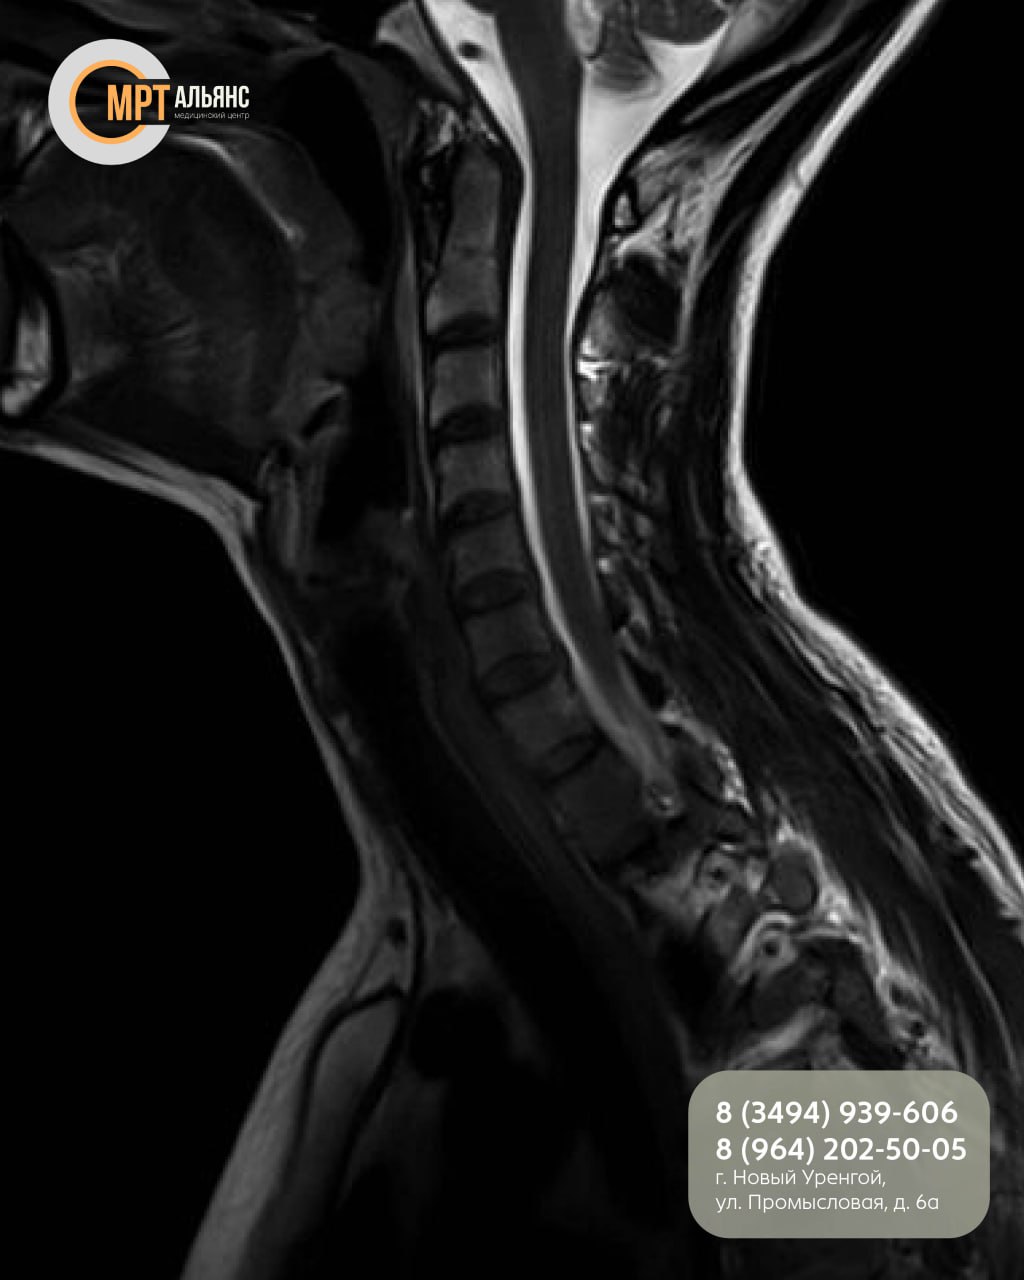

МРТ шейного отдела детально показывает:

· Позвонки и межпозвонковые диски

· Позвоночный канал и спинной мозг

· Нервные корешки и межпозвонковые суставы

· Состояние мягких тканей

Исследование позволяет точно диагностировать протрузии, грыжи, остеохондроз и последствия травм!